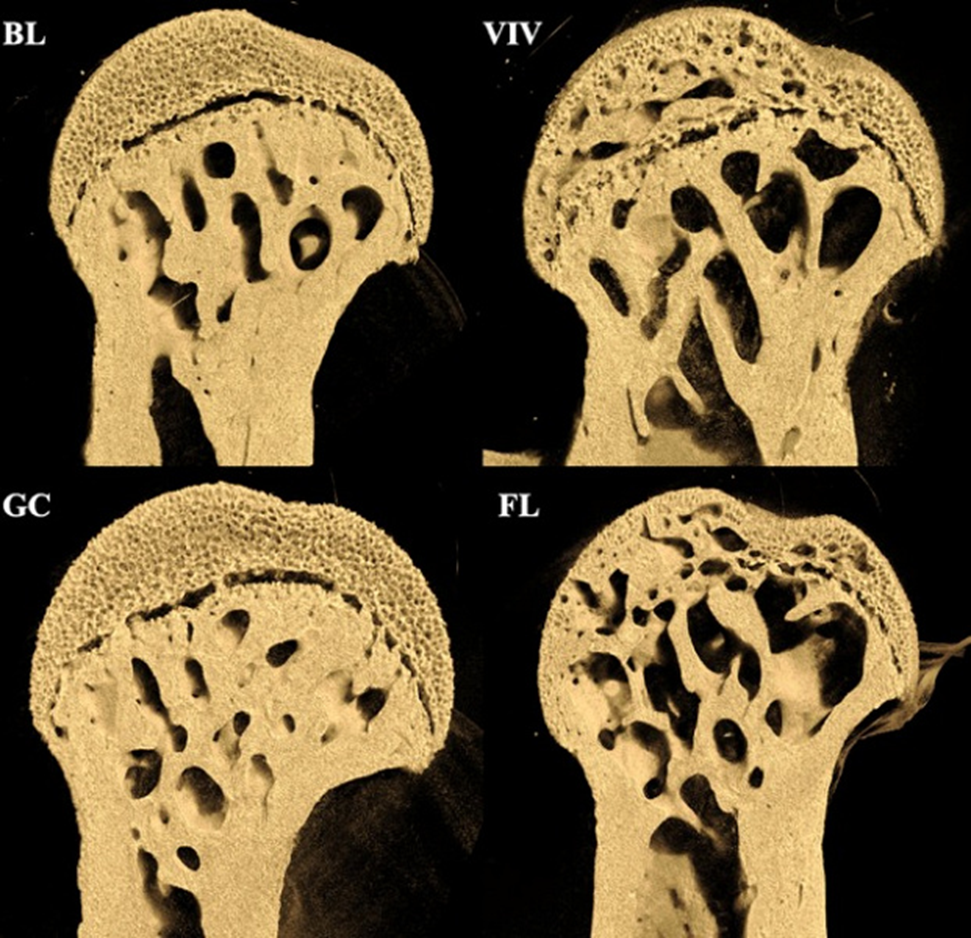

Шейка бедренной кости наземных контрольных мышей GC и VIV, и мышей, побывавших в космосе FL и BL. Фото: NASA

В эксперименте 37 мышей провели месяц на орбите, причем отдельные партии в разное время. Анализ их скелетов выявил значительную деградацию в зонах, которые на Земле выполняют несущую функцию. Бедренные кости грызунов, особенно области соединения с тазом и коленом, потеряли до 18% губчатой ткани, в то время как поясничный отдел позвоночника, не участвующий в поддержке веса, остался практически без изменений. Для контроля группа мышей на Земле прошла симуляцию стресса от запуска, но не подвергалась микрогравитации.

Если бы радиация или системные факторы доминировали, то было бы равномерное воздействие на скелет. Однако разрушение происходит избирательно, концентрируясь в точках, которые в обычных условиях испытывают максимальную нагрузку. Например, шейка бедра, защищённая плотным кортикальным слоем, потеряла до 25% внутренней губчатой структуры, что противоречит теории о влиянии радиации, которая должна воздействовать прежде всего на поверхностные слои.